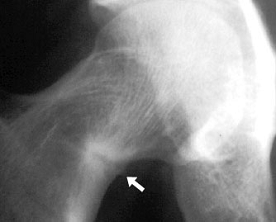

диагностическое значение принадлежит рентгенологической картине. Остеомаляция

костей характеризуется обеднением солями кальция, искривлениями костей и

наличием зон перестройки Лоозера (Looser) [синдром Милькмана (Milkman)].